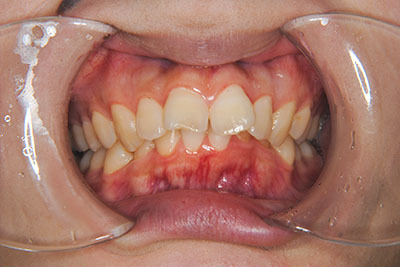

おとなの方でも矯正治療をあきらめないでください!

矯正歯科治療は子供の頃だけしかできない……

子供の頃に比べ大人になったら治療期間がすごく長い……

というようなイメージをお持ちではありませんか?

子供の頃に矯正治療を行う方が治療期間が短く済むというのは、確かですが、矯正治療は患者様の意識も重要です。

いくら歯が動き易くとも、本人がやる気でなければ効果は出ませんし、むし歯発生のリスクも高まります。おとなの方は顎の成長が終わっているため、治療の計画が立てやすいとも言えます。「もう大人だから…」とあきらめず、一度ご相談ください。